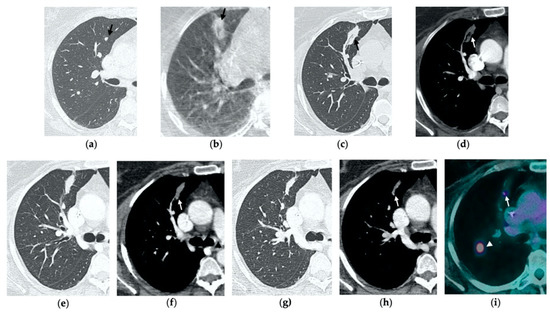

Figure 1. 74-year-old man with a pulmonary metastasis from bladder urothelial carcinoma. (a) Cone-beam CT image of the left upper lobe metastasis (black arrow) prior MWA. (b) Cone-beam CT image obtained post-procedure shows hazy GGO of the ablation site surrounding the treated nodule (black arrow) and a small layer of lateral pneumothorax (arrowhead). (c) Axial 1-month follow-up CT image shows a large consolidation with inner cavitation (black arrow). (d,e) Axial 3-month follow-up CT image shows resolution of the cavitation and decrease in size of the consolidation (black arrow) (d) and demonstrates peripheral mild enhancement with no central contrast material uptake (white arrow) (eg). Axial (f) and coronal (g) CT images obtained after 10 months show a residual fibrotic band (black arrow).

3.2. Contrast-Enhanced CT at 1 Month

By the first month after MWA, the rim of parenchymal GGO has dissolved in most patients as a result of regressing parenchymal edema, inflammation and hemorrhage, and the ablation site appears as an area of consolidation with a mean diameter still larger than the preablation zone (Figure 3c,d and Figure 4c,d) [21]. It is, therefore, crucial in this phase to measure the area of consolidation by its maximum axial diameter in order to thoroughly compare it during the following phases [7]. The consolidation may demonstrate inner cavitation or a central hypoattenuating area with reduction in contrast material uptake, along with a mild peripheral enhancement layer as an expression of reactive hyperemia, which should present smooth with linear margins (Figure 1c) [7,15]. This phenomenon must be referred to benign periablational enhancement and it should be differentiated from pathological contrast uptake, which is usually more irregular and nodular-shaped [7]. It is, therefore, pivotal to perform CT before and after contrast material administration in order to adequately evaluate the enhancement features of the treated tumor. The ablation site may also show hypoattenuating bubbles or a cavity with thin walls, containing solid tissue with reduced contrast enhancement, necrotic material or air-fluid levels, and a communication between the cavitation and a bronchus may be recognized (Figure 2c–e) [7,16]. The latter being a common finding since the necrotic tissue may be evacuated through a bronchus and it should not be mistaken for rare although possible complications, such as an abscess or a broncho-pleural fistula (BPF). Unlike the normal cavitary changes of the ablation area, an abscess is a rare complication (0.5%) [20] and appears as a cavity with thick walls, irregular internal contours and air-fluid level, and must be suspected when fever and laboratory signs of infection are present [22]. Pleural changes are also common findings, especially in peripheral lesions, including pleural thickening in the region of pleura traversed by the microwave antenna, pleural retraction and effusion [15]. Reactive mediastinal lymphadenopathy often occurs at an early stage, and it should not be considered a sign of tumor progression [7,23].

3.3. Contrast-Enhanced CT at 3 Months

On CT images obtained at 3-month follow-up, the size of the ablation zone should be the same or still larger than the baseline tumor, although it undergoes further involution compared to the early phase, as during the fibrosis process the wall thickness and the previously depicted cavities progressively decrease (Figure 1d) [7]. The attenuation of the ablated tissue decreases, as there is no more central contrast material uptake in relation to the local necrotic changes, while the peripheral benign enhancement may persist or decrease (Figure 1e). Overall, the size of the ablation area at this stage should become stable along with a decrease in wall thickness [7,8].

3.4. Contrast-Enhanced CT at 6 Months

After 6 months, the ablation site undergoes further involution and there should not be any inner contrast enhancement, except for the persistent benign periablational area (Figure 2f,g) [7]. The previously mentioned cavities decrease in size and may completely disappear. CT images may show fibrotic scarring without contrast enhancement and mild architectural parenchymal distortion of the surrounding lung (Figure 1f,g) [24]. At this stage, small treated nodules may already show a linear fibrotic evolution on CT images (Figure 2h,i).